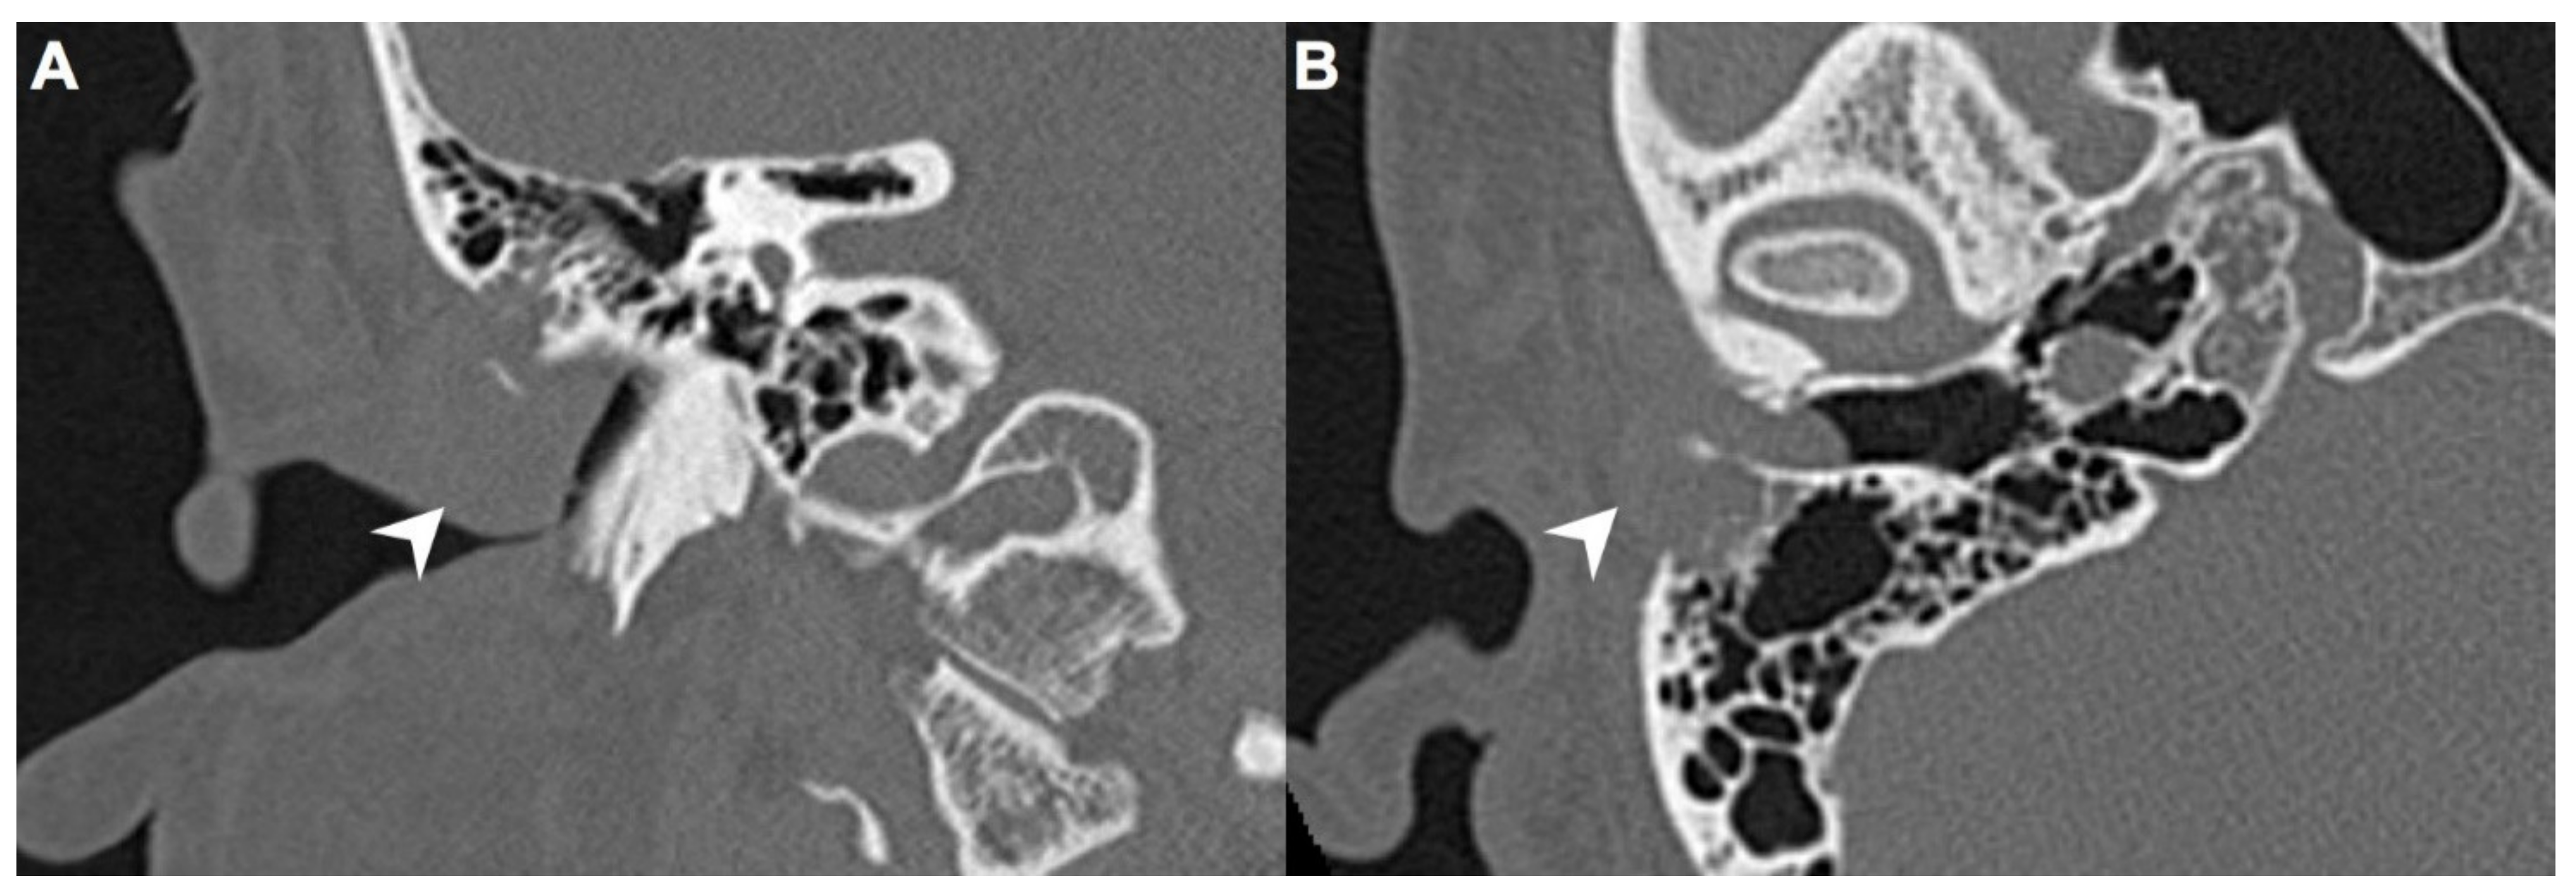

A 40-year-old male with hypertension was taking appropriate medication. He had suffered from right hearing impairment and aural fullness for two months. Examination with an otoscope revealed a smooth bulging mass with a non-epithelial defect on the right side that totally occluded the EAC (Figure 1). No otalgia, otorrhea, vertigo, or facial palsy was noted. There were no other lesions in the head-and-neck region. Audiological assessment revealed conductive hearing loss (pure-tone average) of 30 dB and an air-bone conduction gap of 20 dB on the right side, with preservation of bone conduction hearing. The laboratory data revealed a mildly elevated C-reactive protein level (7.44 mg/L; normal <5 mg/L) without leukocytosis (5400/µL; normal 3900–10,600/µL). As the EAC was occluded, high-resolution computed tomography (HRCT) was scheduled and revealed a submucosal soft tissue mass accompanied by partial mastoid bony destruction (Figure 2A,B). Magnetic resonance imaging (MRI) revealed a well-circumscribed mass in heterogeneous T1-weighted hyperintense (Figure 3A) and T2-weighted isointense (Figure 3B) images.

In our patient, HRCT of the temporal bone revealed a well-demarcated, submucosal nodular lesion in the right EAC with tiny bony internal fragments (Figure 2A,B). MRI is indicated when HRCT shows a tumor involved with adjacent EAC soft tissues. In our patient, MRI revealed a well-circumscribed mass in the EAC that was hyperintense in the T1 (with contrast) sequence but T2-isointense (Figure 3A,B). Noda et al., and Pons et al., reported similar findings; T1-weighted contrast-enhanced MRI enabled strong tumor enhancement [10,11].

Figure 2. (A) On high-resolution computed tomography (HRCT), right EAC was occupied by a mass (arrow) on coronal view. (B) This submucosal soft tissue mass (arrow) was accompanied by partial mastoid bony destruction on axial view.